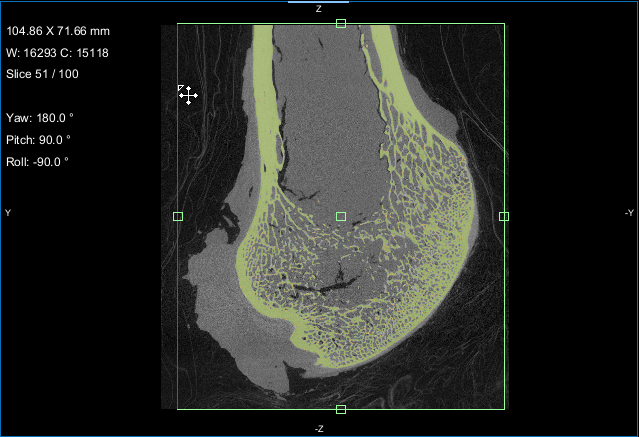

Screen capture of the completed tutorial

Comparison of volume fraction scalar map (on left) with vector-based field of anisotropy (on right)